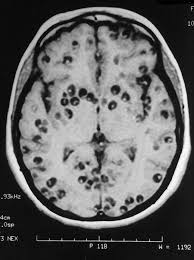

La neurocisticercosis es la más importante localización de la cisticercosis. Los cisticercos se pueden localizar en muchas partes del organismo, pero en la mayoría de los casos comprometen el SNC. Después de esta localización le siguen en frecuencia, el tejido celular subcutáneo y los ojos. El número de vesículas puede ser múltiple, aunque en ocasiones se observan muy pocas o sólo una. En el SNC puede invadir cualquiera de sus estructuras. La localización más frecuente es en el parénquima de los hemisferios cerebrales, seguido de las cavidades ventriculocisternales principalmente el IV ventrículo, espacio subaracnoideo, las meninges y la médula. La cisticercosis múltiple es más frecuente que la única. La forma racemosa prefiere las cavidades, en las cuales adquiere diferente forma y tamaño. La inflamación de los tejidos, principalmente en SNC, se presenta con mayor intensidad cuando los quistes mueren, bien sea espontáneamente o por tratamiento. En estos casos, en la vecindad de los cisticercos se presenta una reacción inmunológica con exudado, inflamación, periarteritis y endarteritis, que puede obliterar la luz de los vasos, obstruir los conductos del LCR y causar hipertensión intracraneana e hidrocefalia.

En algunas localizaciones produce lesiones en los pares craneanos. La meningitis por cisticercosis produce engrosamiento de las membranas y abundante exudado. Si está comprometida la aracnoides, se pueden afectar los pares craneanos de la base y contribuye a la obstrucción del LCR. La invasión de la médula espinal es poco frecuente. Se ha descrito una forma miliar con múltiples cisticercos pequeños que se localizan principalmente en el parénquima cerebral, en cuyo caso se produce encefalitis. Debido a la gran inflamación difusa, es posible que no se observen los quistes en la escanografía. En cuanto a la localización dentro del SNC, se ha encontrado que aproximadamente la mitad están en los hemisferios, una tercera parte en las cisternas, una cuarta parte en los ventrículos y aproximadamente 5% en la médula espinal. Las lesiones múltiples son dos veces más comunes que las únicas en los hemisferios y cisternas, mientras que en los ventrículos es más frecuente la presencia de quistes únicos. Excepto en el cerebro y en el ojo, los cisticercos vivos están rodeados por una cápsula fibrosa, fácilmente desprendible del tejido que los rodea.

Mientras estén vivos presentan mecanismos de adaptación al huésped que les permite una vida muy larga, hasta más de 20 años, y poca reacción inflamatoria periquística. Al morir se degeneran en una masa amorfa, rodeada de células gigantes, histiocitos, células epitelioides, linfocitos y eosinófilos, que progresivamente se va fibrosando y termina por calcificarse. Como el promedio de vida de los quistes es muy variable, lo más frecuente es encontrar en el mismo paciente, cisticercos vivos, en vía de destrucción y calcificaciones. Las manifestaciones clínicas y el pronóstico dependen si los quistes están activos o muertos, de la respuesta immune, del número (único o múltiple) y la localización. El periodo de incubación ha sido estimado en promedio 3,5 años. La neurocisticercosis presenta manifestaciones neurológicas y/o psiquiátricas. Las más frecuentes son la cefalea crónica severa y la epilepsia con convulsiones focalizadas. Las alteraciones neurológicas comprenden signos piramidales, disfunción cerebral, ataxia, movimientos involuntarios y déficits sensoriales. La forma más grave de presentación es la encefalitis cistercósica que ocurre en niños y mujeres jóvenes. Las alteraciones psiquiátricas tienen un amplio espectro, desde las deficiencias intelectuales a la demencia. Existen muchos casos asintomáticos con invasión del SNC (13 a 50% según diferentes publicaciones), en los cuales la presencia de los cisticercos fue un hallazgo de autopsia. De acuerdo a las localizaciones principales, describimos la sintomatología. En las formas que afectan el SNC la sintomatología es muy variada y está determinada por la localización, el número de parásitos y la respuesta inmunológica. La enfermedad puede ser aguda o crónica y el período de incubación varía de pocos meses a muchos años. No existe sintomatología típica y lo más frecuente es la presencia concomitante de varios síndromes.

El diagnóstico es epidemiológico (antecedente de consumo de carne porcina cruda o insuficientemente cocida y por métodos auxiliares. En la teniasis intestinal se realiza por la eliminación de proglótidas móviles (5-7 mm ancho por 20 mm de largo) en materia fecal o en la ropa interior. En este caso deben ser recogidos en formol al 5% para su identificación. El examen parasitológico seriado con método de enriquecimiento por sedimentación debe ser complementado con la prueba de Graham que permite observar los huevos depositados en la zona perianal. En el recuento y fórmula leucocitaria pueden observarse leucopenia y eosinofilia (hasta 28 %). En la neurocisticercosis se utilizan: El diagnóstico por imágenes: tomografía axial computada y resonancia magnética nuclear; El diagnóstico por detección de anticuerpos específicos en sangre y LCR, la técnica de ELISA (sensibilidad 44-74 %), Western blot (sensibilidad 90-100 % si tiene más de dos quistes) y de corresponder, biopsia de cerebro para estudio histopatológico. Utilizando el método de inmunoelectrotransferencia se han identificado entre 30 y 50 antígenos diferentes producidos por los cisticercos, que reaccionan con los anticuerpos de pacientes con cisticercosis. Muchos de estos antígenos producen reacciones cruzadas con otras helmintosis.

Existen mecanismos de evasión inmune en la cisticercosis, contra los eosinófilos y los macrófagos, así como por inhibición de linfocitos T. Estos mecanismos dejan de actuar cuando los cisticercos son afectados en su viabilidad, por el tiempo o por tratamientos. En el diagnóstico clínico de la neurocisticercosis, es importante considerar la procedencia del paciente, pues generalmente se conocen las zonas endémicas. La presencia de epilepsia de aparición tardía, de hipertensión endocraneana, de meningitis crónica, etc., deben hacer pensar en cisticercosis y exigen un diagnóstico clínico diferencial con tumor cerebral, obstrucción venlricular de otro origen o cualquier causa de compresiones en tejido cerebral. El electroencefalograma presenta cambios en la mayoría de los casos, pero es de poca utilidad para el diagnóstico diferencial. Los estudios que se deben realizar en un paciente sospechoso de neurocisticercosis son: Estudios radiológicos (Escanografía o Tomografía axial computarizada (TAC) y la resonancia magnética (RM) son los métodos más utilizados en la actualidad.

La RM es más sensible que la TAC. al reconocer mejor el edema perilesional y los cambios degenerativos del parásito, así mismo los quistes intraventriculares o cerebelosos y las formas racemosas en las cisternas de la base y la fosa posterior. Permite también visualizar mejor el escólex dentro del quiste, como un punto de mayor densidad. Las calcificaciones se aprecian mejor por la TAC. Desde hace muchos años se utilizó la fijación del complemento, la cual fue seguida por la hemaglutinación indirecta. Estos dos métodos fueron remplazados por la prueba inmunoenzimática (ELISA), que se usa ampliamente en la actualidad, aunque tenga una eficacia moderada y la prueba de preferencia es el inmunoblot o western blot. La droga recomendada es Praziquantel en dosis única de 10 mg/kg y la curación estadísticamente probada, es del 88-100 %. Se elimina por la leche, por lo tanto, la madre no debe amamantar por 4 días. Es escasa la experiencia en menores de 4 años. Las drogas alternativas son: Nitazoxanida, con una eficacia es del 90 %. No se puede utilizar en niños menores de 3 años, gestación y lactancia. El Albendazol está contraindicado en epilepsia, embarazo y lactancia. No hay experiencia de uso en menores de 2 años. La Niclosamida y la Paramomicina, completan la lista de alternativos. En casos de cisticercosis calcificada no se justifica el uso de antiparasitarios. Debido al amplio uso de los dos antihelmínticos, efectivos en la mayoría de los quistes intraparenquimatosos, se ha limitado el tratamiento quirúrgico. Son indicaciones quirúrgicas también los quistes solitarios del IV ventrículo, quistes de otros ventrículos o de la médula espinal y algunos subaracnoideos. La cisticercosis es una parasitosis propia de países subdesarrollados y como todas las infecciones producidas por contaminación fecal. La defecación en la tierra donde existan cerdos que consumen materias fecales humanas y el mal saneamiento ambiental unido a deficiente higiene personal, son los factores que facilitan la presencia de cisticercosis.